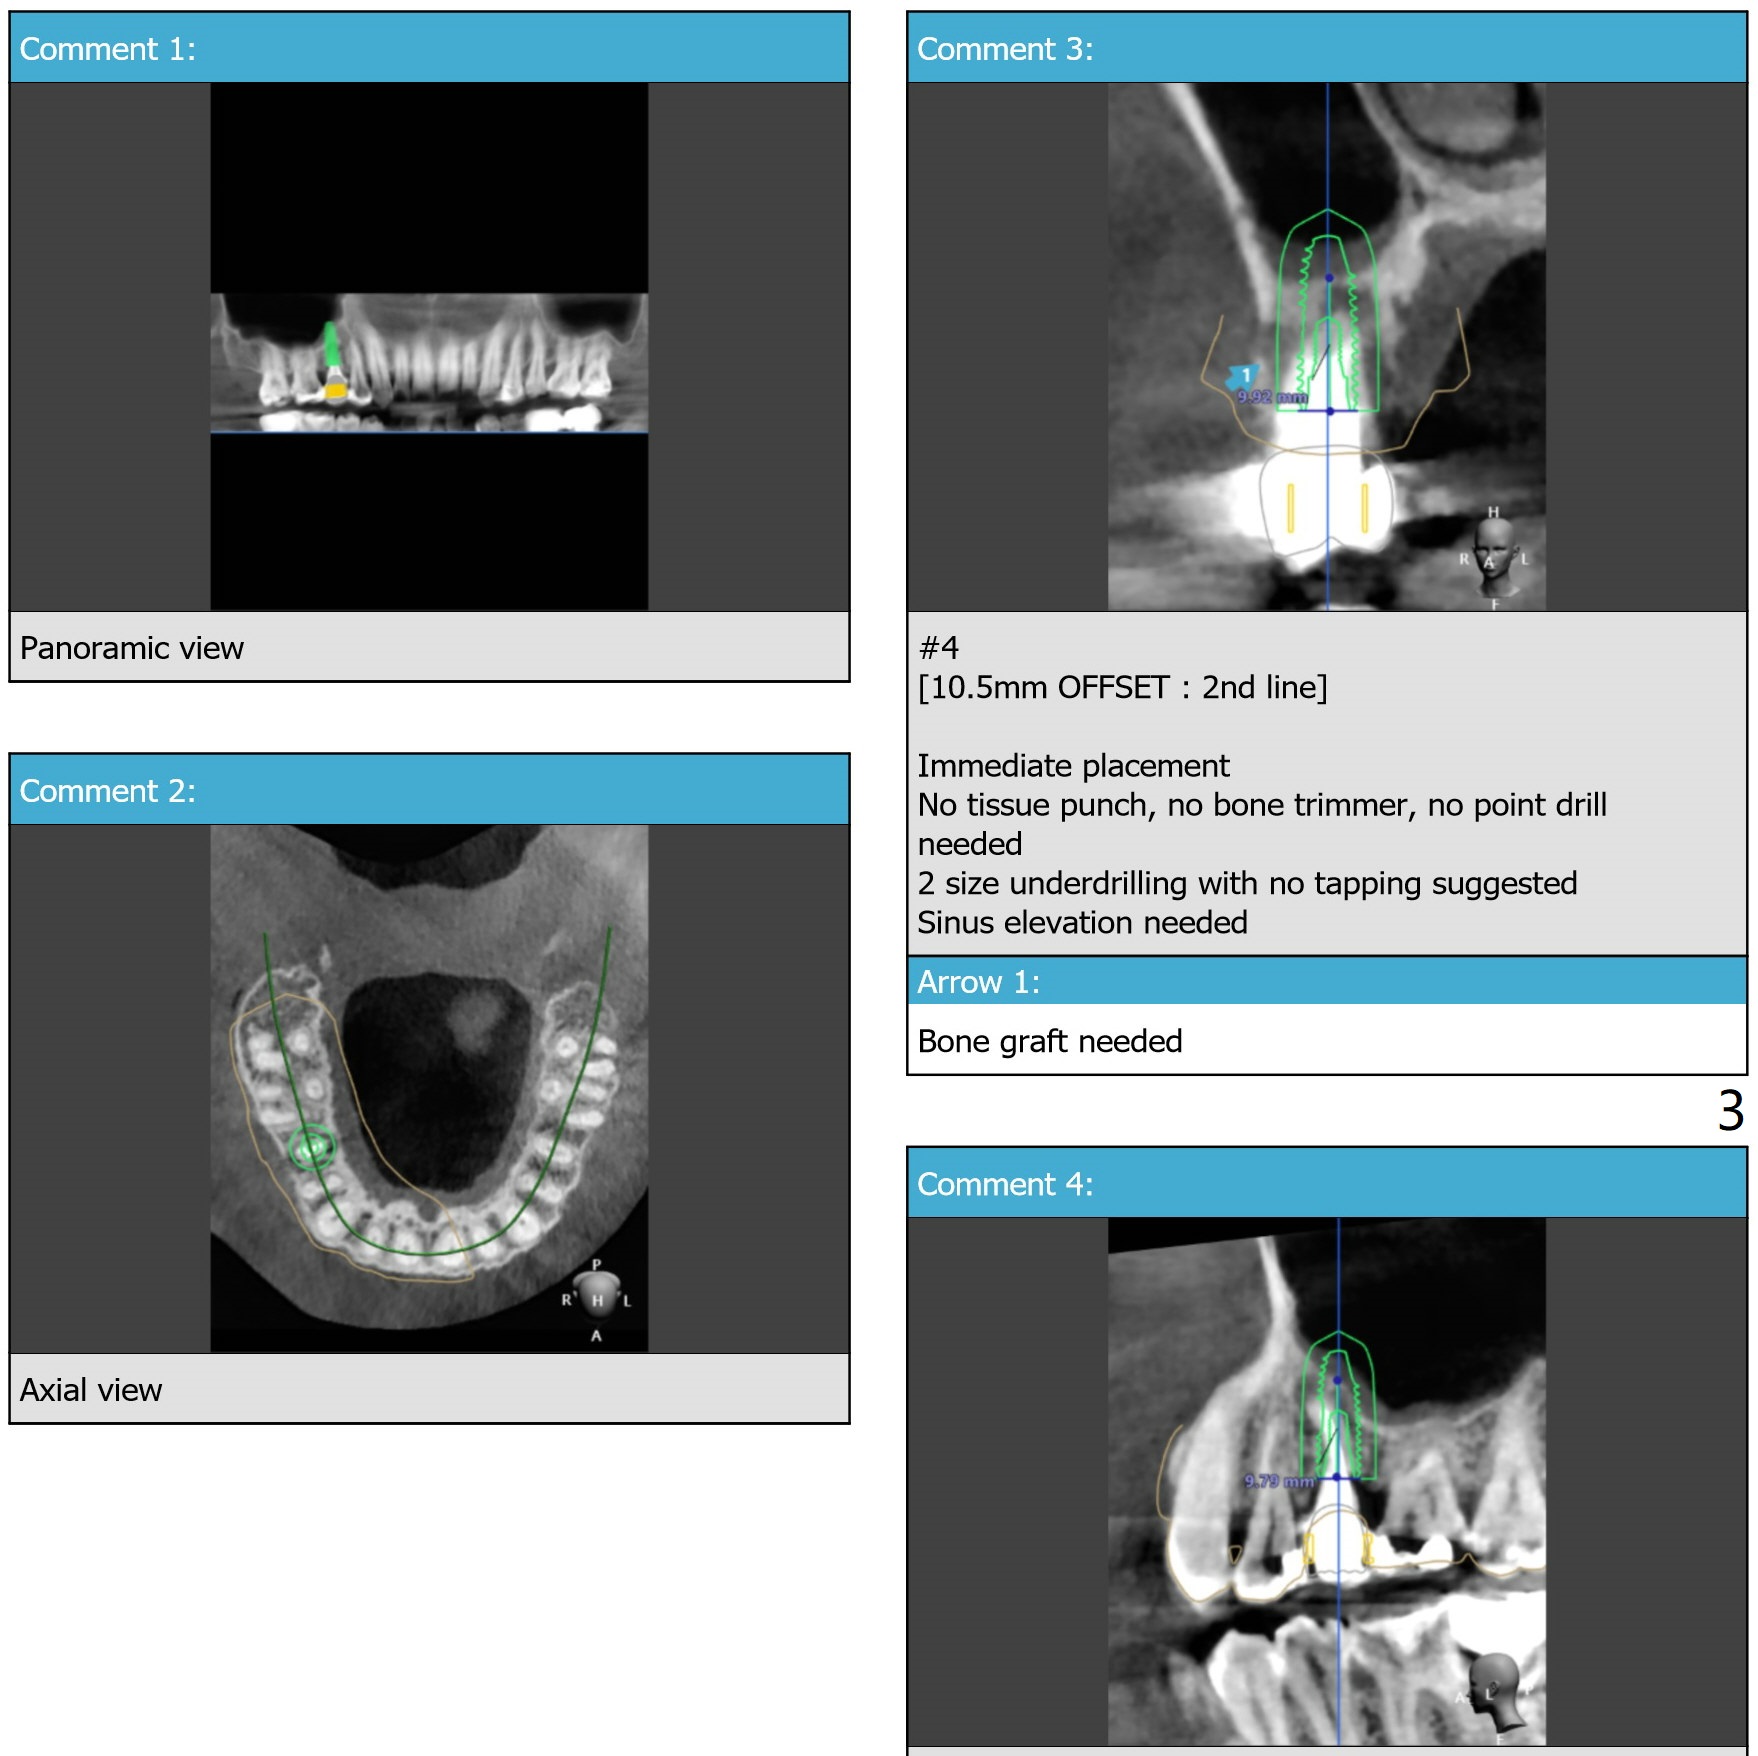

Sinus Lift-Minimal Apical Bone

While the doctor is using the last drill (3.0x8.5 mm), measure the length of 2.2x8.5 mm drill. If it is less than 19 mm, use 19 mm sinus lift drill of DIO Sinus Approach Kit. Otherwise, use 2.2x10 and 2.2x11.5 mm drills if necessary. Prepare water lifter.